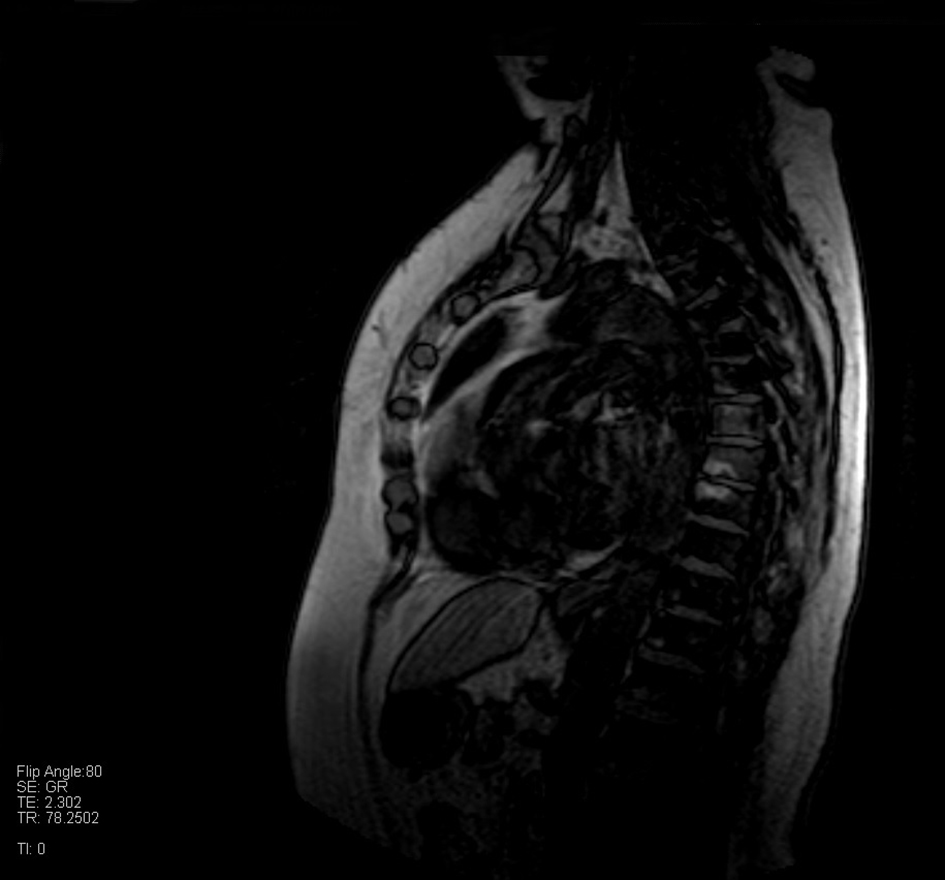

We report a clinical case of a 75-year-old woman, with a history of breast cancer who undergone surgery 7 years ago, presenting bone metastases in different areas. The lesion was found by a routine mammography 7 years ago and she was operated few months after the discovery. After 7 years of clinical silence from the diagnosis, the patient was submitted to a positron emission computed tomography (PET/CT) that showed multiple predominantly lytic lesions in several skeletal segments, especially to the left iliac wing and ipsilateral acetabulum, at the level of the right scapula and L4 and D10 vertebra. This result led to a palliative radiant treatment at the level of the L4 vertebrae with a total dose of 30 Gy in 10 fractions (3 Gy/fraction) provided with a 6 MeV flash technique. After 2 months from the treatment, a total body CT was performed and it confirmed the previous lesions seen in the PET/CT and showed new lesions to the vertebra from D1 to D5. A further CT few months later pointed out an unchanged condition but there was also a worsening of the lytic lesions in D3 and D4, confirmed by an MRI 1 month later (Fig. 1). In February 2016, this woman arrived at our structure for a palliative treatment for the pain she felt at the level of her back and right scapula. We visited the patient and evaluated the pain level in the different sites through a numeric scale of evaluation (Karnofsky scheme) and an objective examination. After evaluating her clinical conditions and viewing the radiological exams, we decided to treat firstly the D2-D6 vertebra with a total dose of 30 Gy in 10 fractions (3 Gy/fraction) and then the scapula with a singular dose of 8 Gy provided with a 6 MV flash technique, where the patients felt the stronger pain, and not to treat the other lesions in areas where the pain was minimal or not existent. This way we save the opportunity to treat them when the patient will become symptomatic.

![]() Click for large image | Figure 1. MRI shows signal alterations at the level of vertebrae from D1 to D5. |